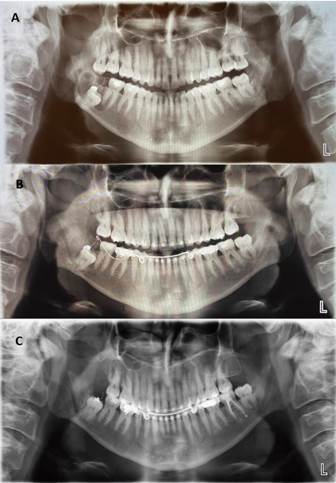

En la radiografía panorámica en el cual se hizo el hallazgo (Figura 1), se observa una imagen radiolúcida, redondeada, de límites definidos en relación a la corona del diente 4.8, que está incluido. En la tomografía computarizada cone beam, tomada al ingresar a nuestro servicio, se observa progresión de la lesión, con desplazamiento de la pieza dentaria a borde basilar mandibular. También es posible observar que este aumento de volumen respeta la anatomía mandibular, no perfora tablas ni hay evidencia de rizalisis (figura 2).

Se hizo un seguimiento semanal del paciente durante el primer mes, luego mensual hasta completar 12 meses. En cada control se evaluaba el estado de la conexión, presencia o no de infección y la permanencia del botón de resina en el tercer molar. En caso de rotura del alambre, se volvía a instalar en los controles periódicos (figura 5).